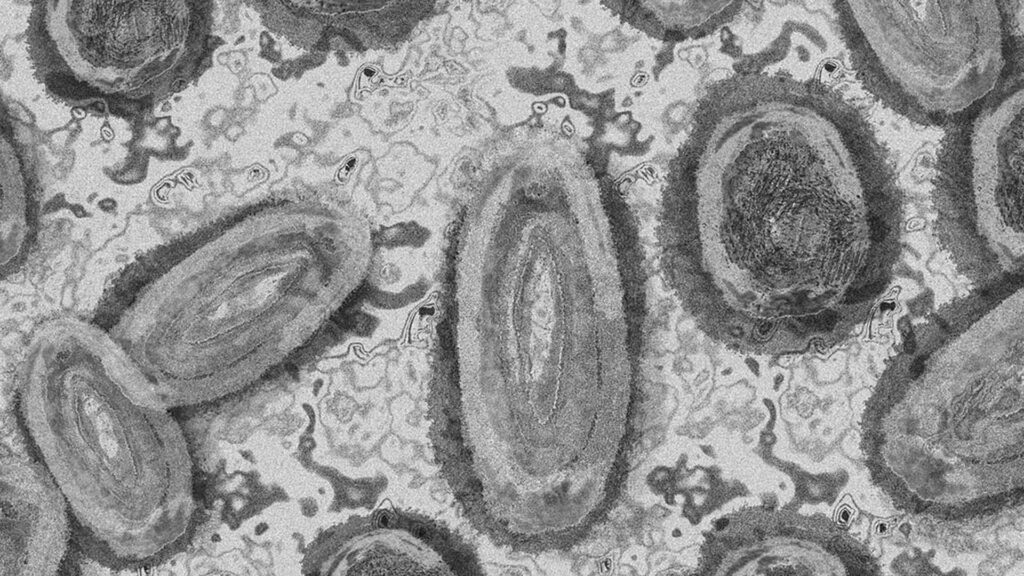

Rare Spread of Monkeypox Puts Health Experts on Alert